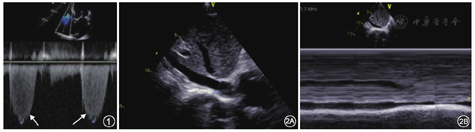

如图1所示,多切面观察使取样线尽量平行于反流束,取得三尖瓣反流的最大流速。通常超声估测的PASP高于右心导管所测值,但在不能获得良好的三尖瓣反流频谱或取样线与反流束夹角过大的情况下时,所测反流速度低估PASP。右心房压力(右房压)的估测见图2和表1,根据下腔静脉(IVC)宽度和呼吸变化率来估算[4],其中下腔静脉在吸气时塌陷,吸气塌陷率=(呼气末IVC内径-吸气末IVC内径)/呼气末IVC内径。

有研究表明,肺动脉瓣反流舒张早期的峰值压差与MPAP高度相关。在无法获取清晰三尖瓣反流频谱的情况下,此方法尤其适用。取胸骨旁短轴肺动脉长轴切面取得肺动脉瓣反流的连续多普勒(CW)频谱,测量舒张早期肺动脉瓣反流速度(Vearly PR)和舒张末期肺动脉瓣反流速度(Vend PR)(图3),可计算MPAP和肺动脉舒张压(PADP),计算公式如下: